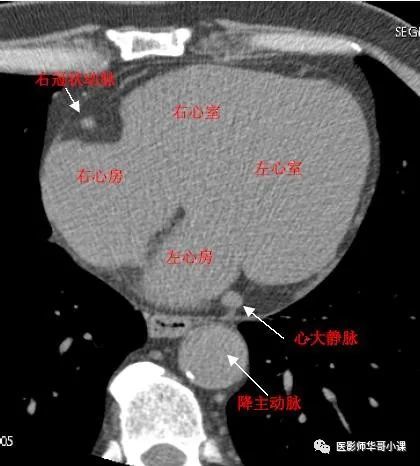

心脏冠状动脉ct解剖中文详细标注(图文) cardiac a

cta冠脉解剖必点收藏

冠状动脉系统解剖,cta解剖,分段及中英文名称对照

冠状动脉系统解剖cta解剖超详细收藏起来随时看